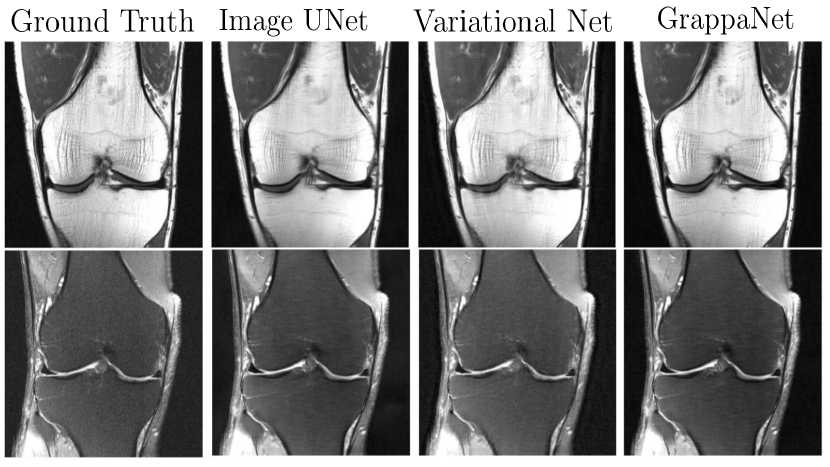

Inverse Mapping for Image Rectification: In CNN based sequential spatial models such as DeepADMM net models (Sun et al., 2016; Schlemper et al., 2017) and Deep Cascade CNN (DCCNN) (Schlemper et al., 2017), the regularization is done in image space using the following set of equations:

Here, and are Lagrange multipliers. The ISTA net (Zhang and Ghanem, 2018) modifies the above image update rule as follows, , using a CNN network . Note that the DeepADMM network demonstrated good performance when the network was trained on brain data but tested on chest data. Later, MODL (Aggarwal et al., 2019) proposed a model based MRI reconstruction where they used a convolution neural network (CNN) based regularization prior. Later, a dynamic MRI using MODL based deep learning was proposed by (Biswas et al., 2019). The optimization, i.e. , denoises the alias artifacts and noise using a CNN network as a regularization prior, and is a trainable parameter. To address this concern, a full end-to-end CNN model called GrappaNet (Sriram et al., 2020b) was developed, which is a nonlinear version of GRAPPA set within a CNN network. The CNN network has two sub networks; the first sub network, , fills the missing k-space lines using a non-linear CNN based interpolation function similar to GRAPPA. Subsequently, a second network, , maps the filled k-space measurement to the image space. The GrappaNet model has shown excellent performance ( PSNR, SSIM) on the FastMRI dataset and is one of the best performing methods. A qualitative comparison is shown in Fig. 10.

Quantitative results are shown in Table 1 for several metrics such as NMSE, PSNR, and SSIM scores. We observe that GrappaNET, J-MoDL and VariationNET outperformed the baseline methods by a large margin. We note that the zero-filled and SENSE reconstructions in Fig 11 (a), (b) show a large amount of over-smoothing. The reconstruction of SENSE and zero-filled model also lack a majority of the high frequency detail that is clinically relevant, but fine details are visible in case of GrappaNET, VariationNET, J-MoDL, and RefineGAN methods. The comparable performance of Deep Decoder and DIP advocates the importance of letting untrained neural network figure out how to perform k-space to MR image reconstruction. The J-MoDL method makes heavy use of training data and the joint optimization of k-space lines and the reconstruction of MR images to get good results both for and as shown in Table 1. On the other hand, the Deep Decoder and DIP methods achieve good performance using untrained networks as discussed in Sec. 5.2, which is advantageous as it generalizes to any MR reconstruction scenario.